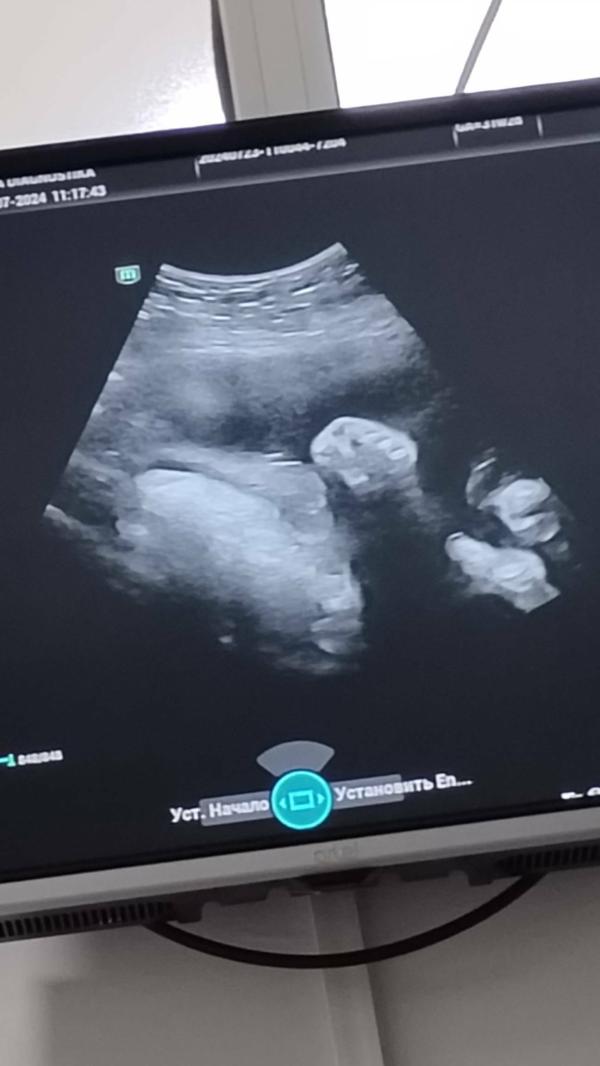

А вот и наш кулачек здоровый и набирающий вес малыш🥰 уже близимся к концу😁 уже не верится в это так быстро время бежит. Все больше усталости😅 но сумки так и не собраны😅 мне говорят что я слишком сильно спешу. Подскажите кто на кокой недельке уже собрал все сумки?😅🙏 И выберали вы заранее род дом. Незнаю стоит ли заранее подобрать или поехать по месту жительства😅 спасибо заранее за обратную связь от вас❤️🥰